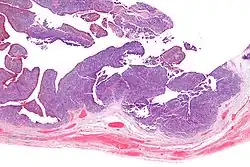

| Micrograph of transitional cell carcinoma of the ovary. H&E stain. |

Transitional cell carcinoma of the ovary (TCC of the ovary) is a rare type of ovarian cancer that has an appearance similar to urothelial carcinoma (also known as transitional cell carcinoma).[1]

TCC of the ovary is diagnosed by examination of the tissue by a pathologist. It has a characteristic appearance under the microscope and distinctive pattern of immunostaining.[2]